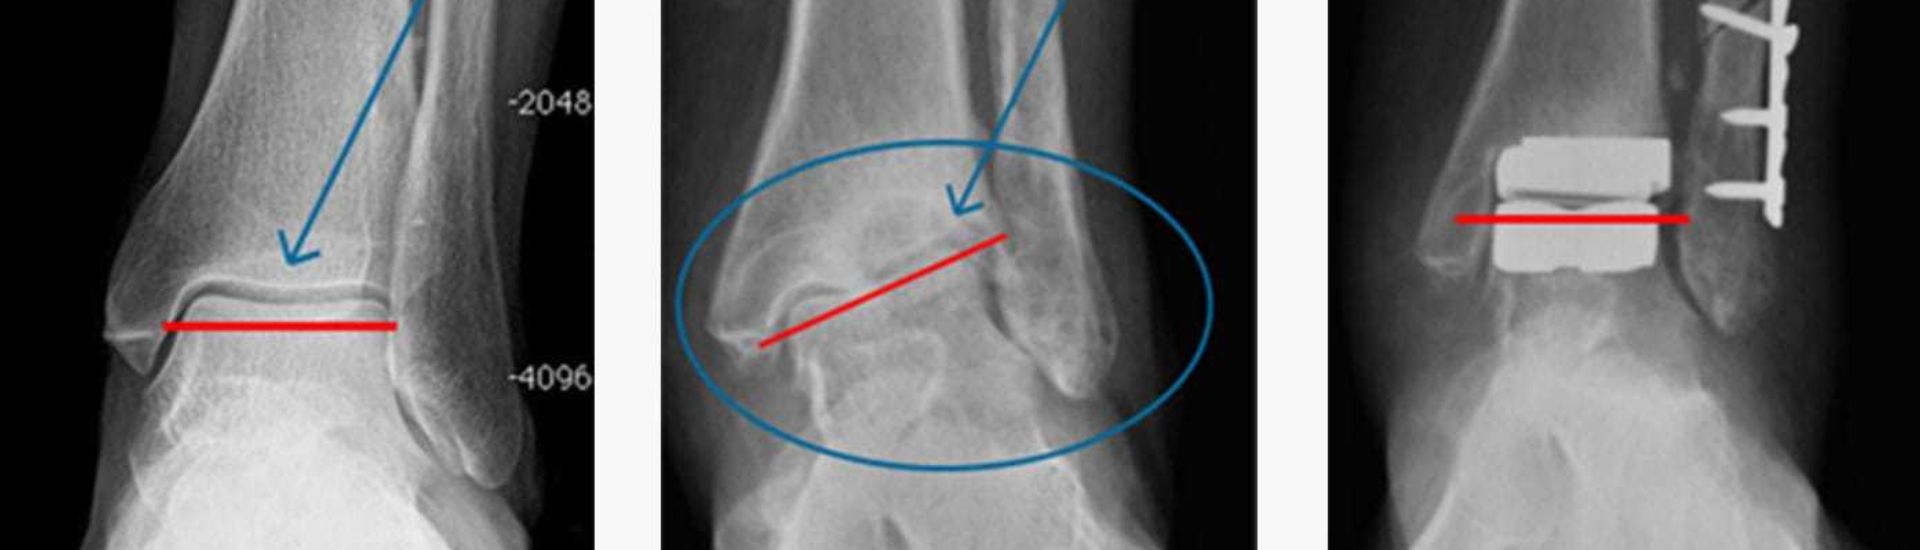

L’RX Tibio-Tarsica è una radiografia mirata all’esame delle ossa e delle articolazioni del piede e della caviglia. Questo esame sfrutta i raggi X per catturare immagini ad alta risoluzione, che mostrano eventuali anomalie come fratture, distorsioni o patologie degenerative. Grazie alla sua precisione, l’RX Tibio-Tarsica rappresenta uno degli strumenti più utilizzati per identificare problemi muscoloscheletrici e alterazioni strutturali in questa zona del corpo.

Durante l’esame, il paziente viene posizionato in modo che la caviglia e il piede siano allineati correttamente per consentire al dispositivo a raggi X di catturare immagini nitide e dettagliate. Il tecnico radiologo guida il paziente attraverso diverse posizioni, come quella antero-posteriore e laterale, per garantire una visualizzazione completa delle strutture. L’esame dura pochi minuti ed è completamente indolore. Le immagini acquisite vengono poi analizzate dal medico per valutare la presenza di eventuali patologie.

Attraverso l’RX Tibio-Tarsica, è possibile ottenere immagini precise delle ossa e delle articolazioni della caviglia e del piede, evidenziando fratture, dislocazioni, tumori ossei e altre alterazioni strutturali. Questo esame consente ai medici di individuare con facilità la presenza di anomalie che potrebbero non essere rilevabili con altre metodiche diagnostiche.